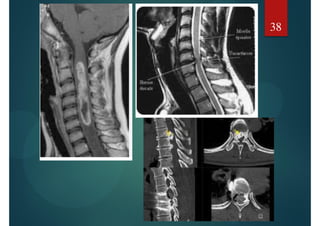

TUMEURS CEREBRALES

Retentissement :

Hydrocéphalie Engagements Cingulaire Temporal

Dilatation du système ventriculaire

Anomalie de la SB périventriculaire

Engagements

Cingulaire

Temporal

Tonsillaire

37

38

TUMEURS CEREBRALES Retentissement : HydrocéphalieEngagements Cingulaire Temporal Dilatation du système ventriculaire Anomalie de la SB périventriculaire Engagements Cingulaire Temporal Tonsillaire 37